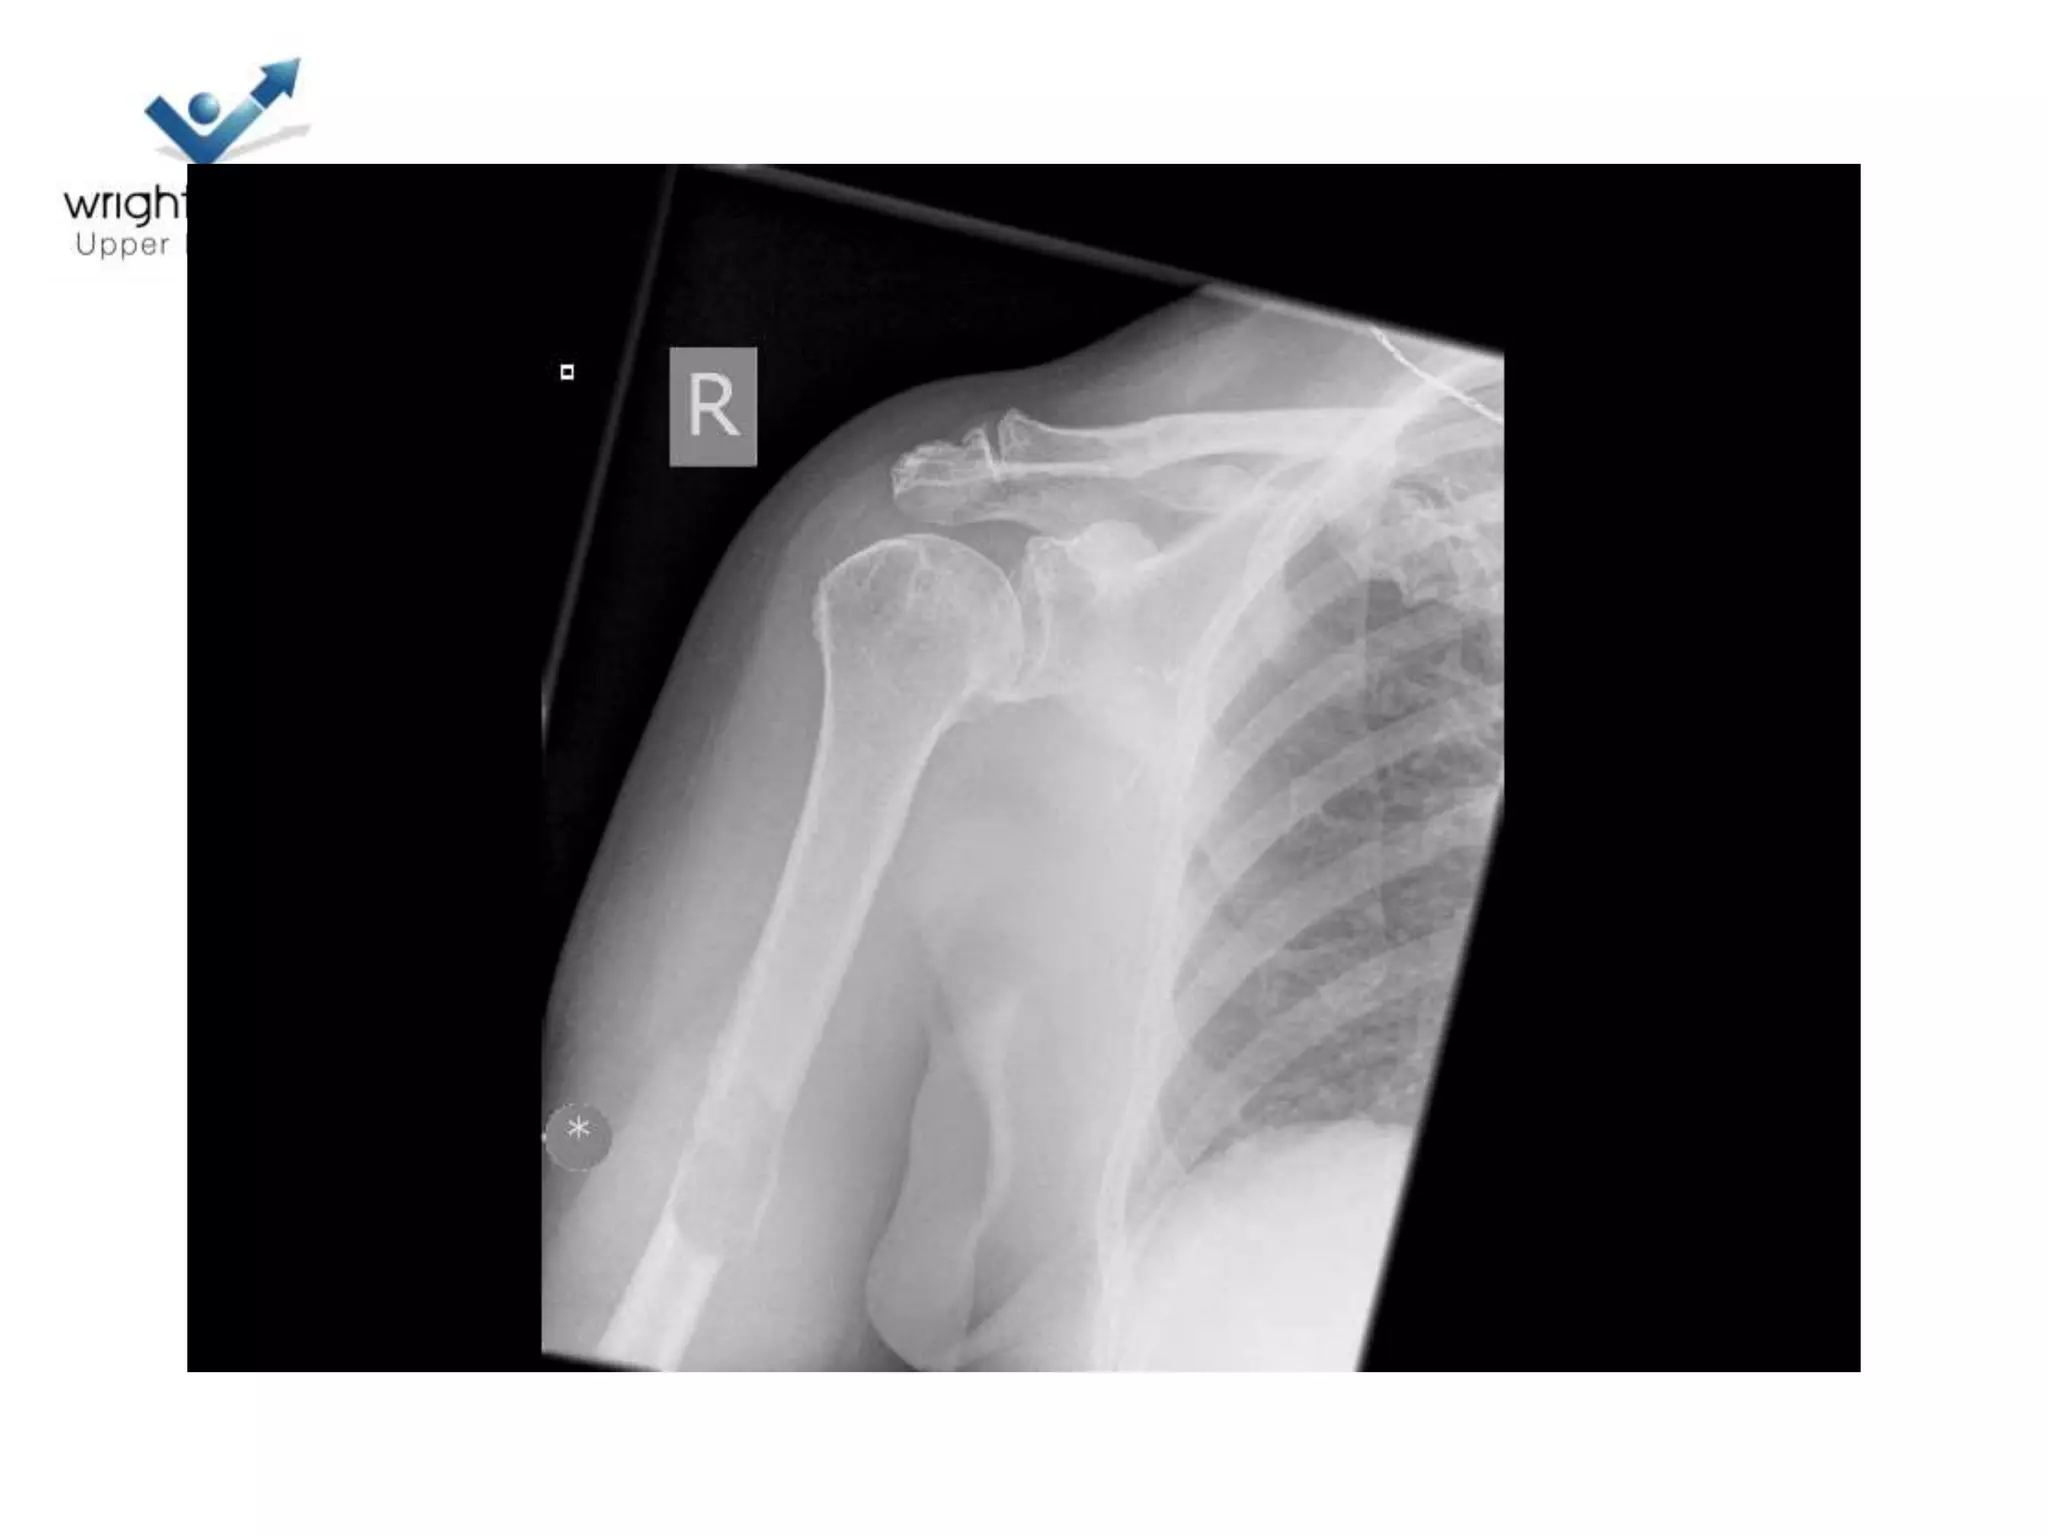

• # dislocations

– If associated with neck

fractures

Indications to operate

• Poor outcome #

– Head splits

– # dislocations ( 4 part)